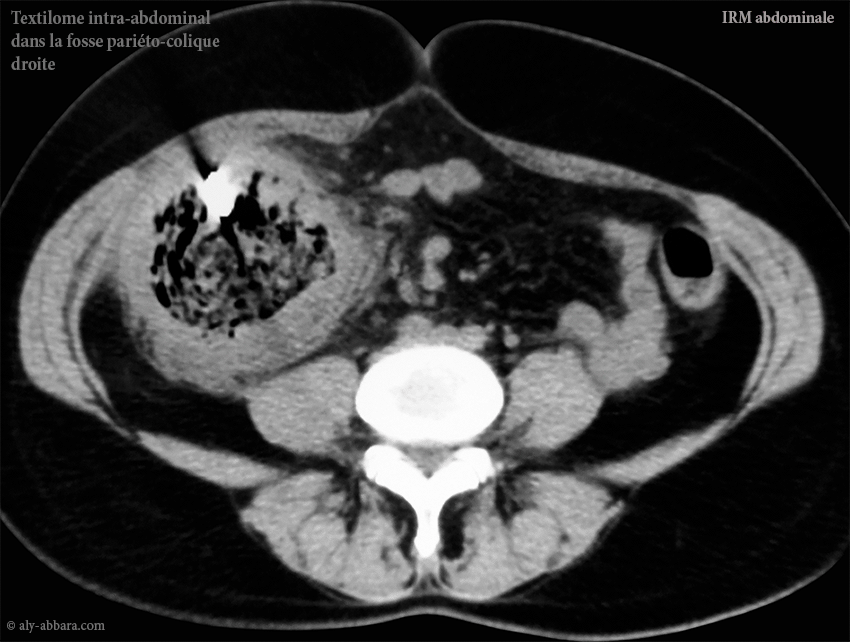

L'aspect par IRM du textilome dans la gouttière pariéto-colique droite

• Cliniquement, la patiente se plaignait d'une douleur chronique localisée dans la région lombaire droite avec une accentuation récente motivant la réalisation d'une IRM abdominale ; cette dernière exploration met en évidence la présence d'un corps étranger occupant la gouttière pariéto-colique droite.

• L'échographie abdominale et l'IRM (Imagerie par Résonance Magnétique) abdominale montrent que ce textilome de découverte tardive (par rapport la date de la réalisation de césarienne) est enveloppé par une épaisse coque de tissu inflammatoire organisé (granulome) ; cette coque est à l'origine de l'enfouissement du textilome qui devient invisible et impalpable lors du premier temps de l'exploration chirurgicale de la cavité abdominale ; donc pour l'extraire il faut préalablement (par imagerie) parfaitement le localiser et connaître ses rapports anatomiques aux organes avoisinants (dans le cas présenté dans cet article : il s'agit du cæcum, du côlon ascendant, de la paroi abdominale latérale droite, de l'épiploon et des anses grêles).